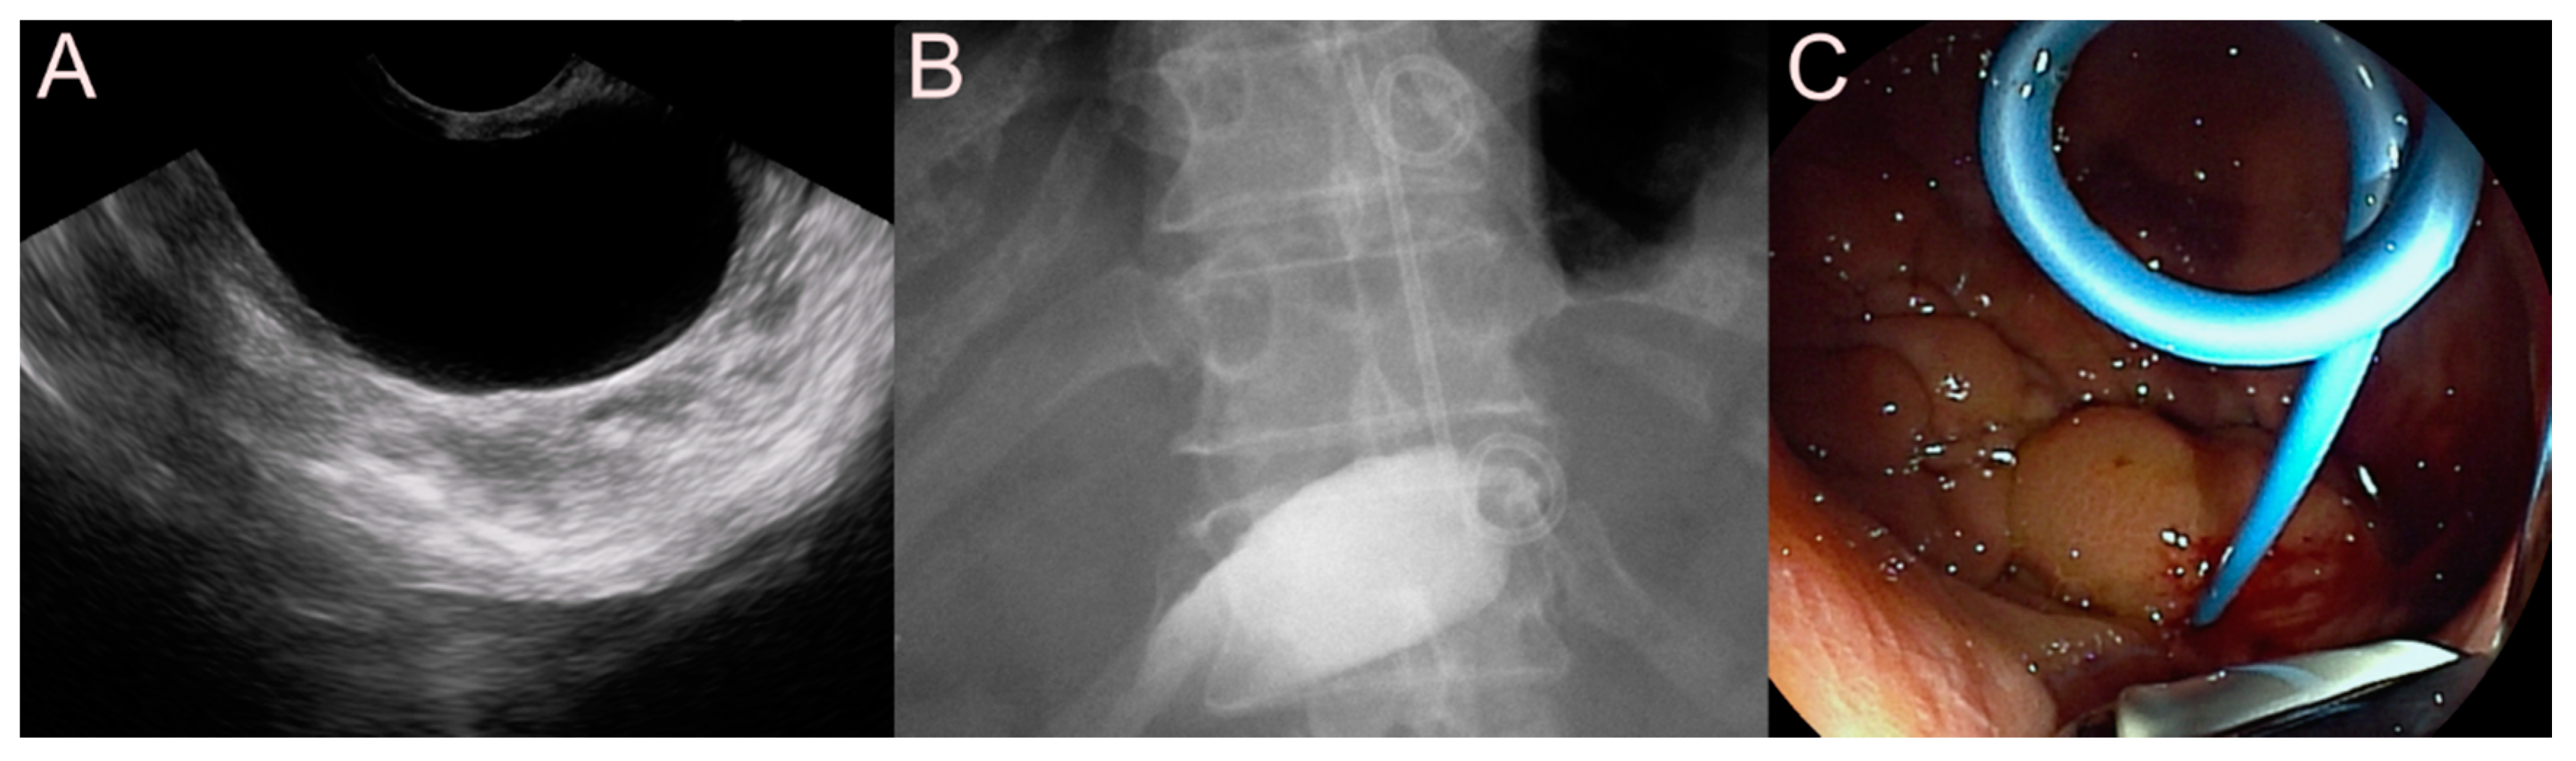

2.3. Stent for EUS-Guided Gallbladder (GB) Drainage

2.3.1. Use of the Plastic Stent

2.3.2. Use of the SEMS

2.3.3. Use of the LAMS